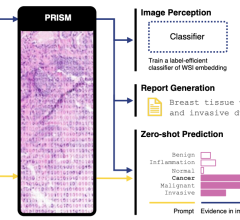

The campus will house large-scale facilities to produce positron emission tomography (PET) imaging agents. When injected into the body, these specialized radiopharmaceuticals, called biomarkers, detect and trace abnormal cellular functions that are associated with a variety of diseases. Visible using sophisticated imaging scanners, these biomarkers make it easier for physicians to non-invasively diagnose critical, life-threatening diseases in their earliest stages. They can also improve physicians’ ability to track the effectiveness of patient treatment plans.

Collaboration laboratory: The center will house “collaborative laboratories” where Cardinal Health will bring industry innovators together with its experts in the fields of scientific research, technology, quality and regulatory affairs and manufacturing. These cross-functional teams will increase the speed of innovation by finding new ways to decrease the time it takes to secure FDA approval of new imaging agents and by sharing best practices for commercialization.

Fully functional, confidential, private guest laboratories: The center will have dedicated, fully equipped laboratories where guest researchers can conduct experiments that will produce, test and develop radioactive products, with the goal of supporting more rapid deployment into large-scale, multi-site clinical trials.